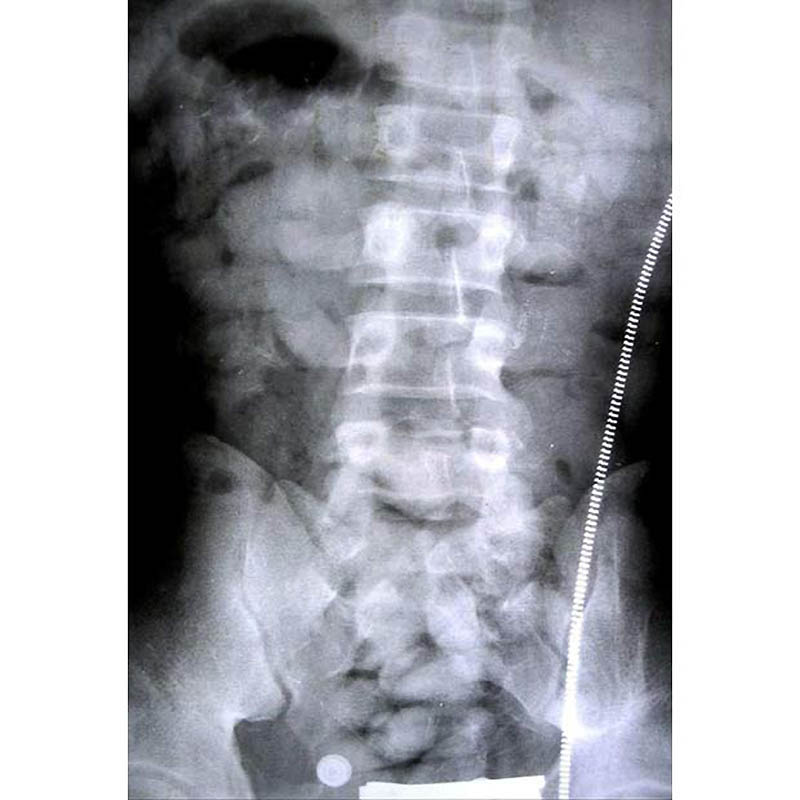

1.Пищеварительная система этого человека была под завязку забита – он пытался провезти в своем теле 150 таблеток.